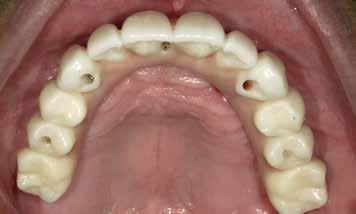

72 FDC 2026 Speaker: Full Arch Implant Reconstruction in the Digital Era: Past, Present and Future